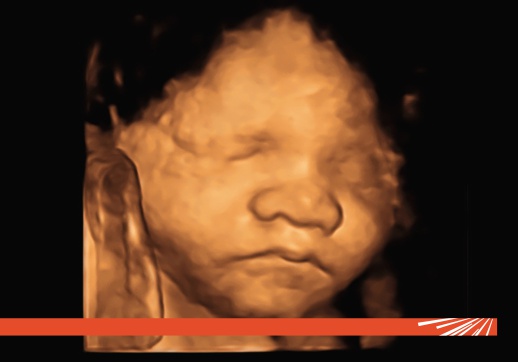

O ecografie morfologică fetală este o examinare cu ultrasunete de înaltă rezoluție, efectuată de un medic specialist în medicină materno-fetală. Scopul principal este acela de a evalua anatomia completă a fătului pentru a detecta posibile malformații structurale sau anomalii de dezvoltare. Spre deosebire de ecografiile obișnuite, care verifică doar ritmul cardiac și creșterea generală, morfologiile analizează fiecare organ și sistem al bebelușului.

Aceasta este cea mai importantă ecografie de sarcină. La această vârstă gestațională, organele sunt suficient de dezvoltate pentru a putea fi vizualizate în detaliu.

Acesta este momentul optim pentru detectarea majorității malformațiilor structurale (cardiace, renale, osoase, cerebrale). Detectarea timpurie permite echipei medicale să pregătească intervenții specifice imediat după naștere sau să ofere consiliere părinților.